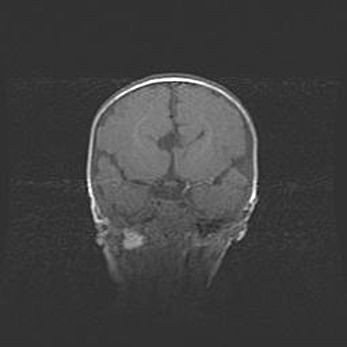

Сообщающаяся гидроцефалия. Кистозная энцефаломаляция головного мозга.

Возраст: 3 месяца 4 дня

Вес: 3100 г

Пол: женский

Окружность головы: 34 см

Срок гестации: 31 неделя

Кистозная энцефаломаляция головного мозга - одна из форм поражения головного мозга в детском возрасте. Характеризуется возникновением множественных и распространённых кист в коре, белом веществе и подкорковых образованиях головного мозга у плодов, новорождённых и детей раннего возраста. Развитие кистозной энцефаломаляции связано с внутриутробной асфиксией и гипотонией, родовой травмой, тромбозом синусов, пороками развития сосудов, инфекциями, сепсисом и другими причинами. Наиболее значимые инфекционные агенты: вирусы простого герпеса, цитомегалии, краснухи, токсоплазмы, энтеробактерии, золотистый стафилококк и другие.